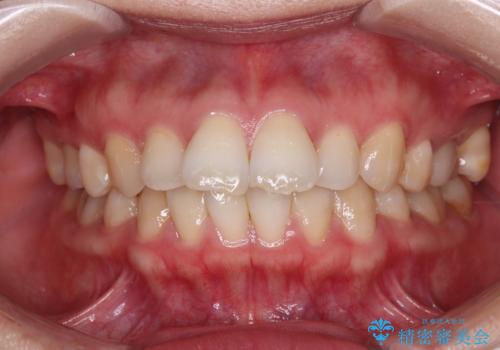

[セラミック治療] 前歯の審美治療に伴う矯正治療